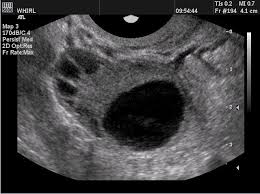

Blind ovum. An ovum with arrested development which may appear as a fluid filled sac with amorphous embryonic rests. A blighted ovum is a fertilized egg that implants itself in the uterus but doesn t become an embryo. The placenta and embryonic sac form but remain empty.

Blighted ovum atau hamil kosong adalah kehamilan yang tidak mengandung embrio. In a normal pregnancy an embryo would be visible on an ultrasound by six weeks after the woman s last menstrual period. A blighted ovum or anembryonic gestation is characterized by a normal appearing gestational sac but.

A blighted ovum also called an anembryonic pregnancy occurs when an early embryo never develops or stops developing is resorbed and leaves an empty gestational sac. There s no growing baby. Dalam dunia medis blighted ovum juga dikenal dengan istilah anembryonic gestation kondisi ini merupakan salah satu penyebab terjadinya keguguran pada trimester pertama kehamilan.

After a week cramps and slight bleeding. The reason this occurs is often unknown but it may be due to chromosomal abnormalities in the fertilized egg. A blighted ovum is a pregnancy in which the embryo never develops or develops and is reabsorbed.